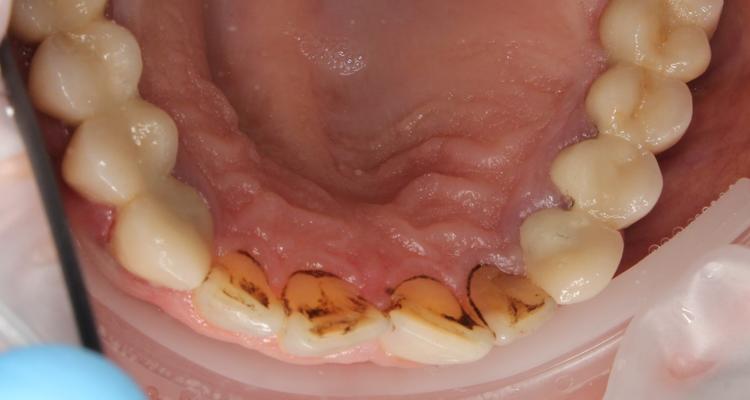

Профессиональная гигиена нижней фронтальной группы зубов

Во время процедуры был удален пигментированный зубной налет и камень, а также проведена полировка зубов.